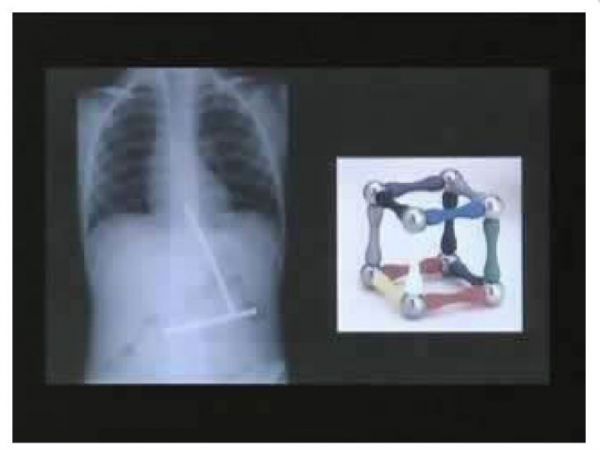

Один маленький мальчик съедал по одной части игрушки с магнитом за раз. Когда наконец все части игрушки оказались в желудке мальчика, они соединились.